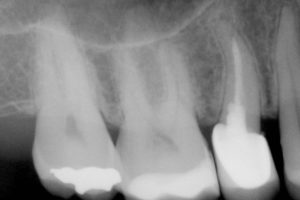

La parodontite è una patologia piuttosto subdola ad eziologia batterica e a patogenesi infiammatoria, conosciuta come piorrea, che – se non curata – porta alla distruzione dei tessuti che assicurano sostegno e stabilità ai denti.

Tale terapia, eseguita dall’igienista dentale, prevede l’eliminazione dei fattori causali della malattia parodontale quali sono i batteri sopra e sottogengivali contenuti nella placca batterica e nel tartaro.Si esegue con strumenti manuali e sonici coadiuvati dall’utilizzo di prodotti capaci di agire in profondità all’interno dello spazio compreso tra gengiva e radice.